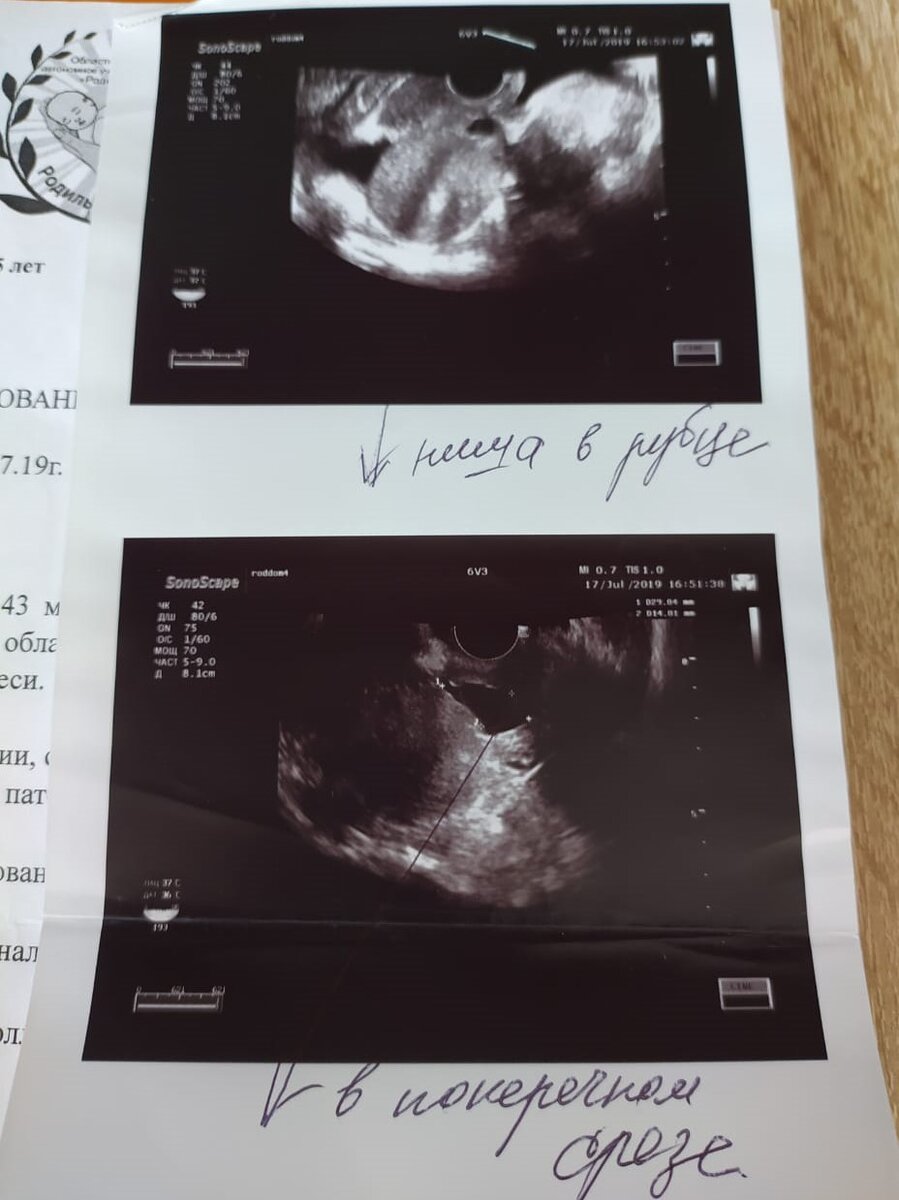

Вот так это выглядит на УЗИ:

фото из личного архива

По УЗИ, которые я делала много раз, размер ниши все определяли по разному. То больше то меньше.